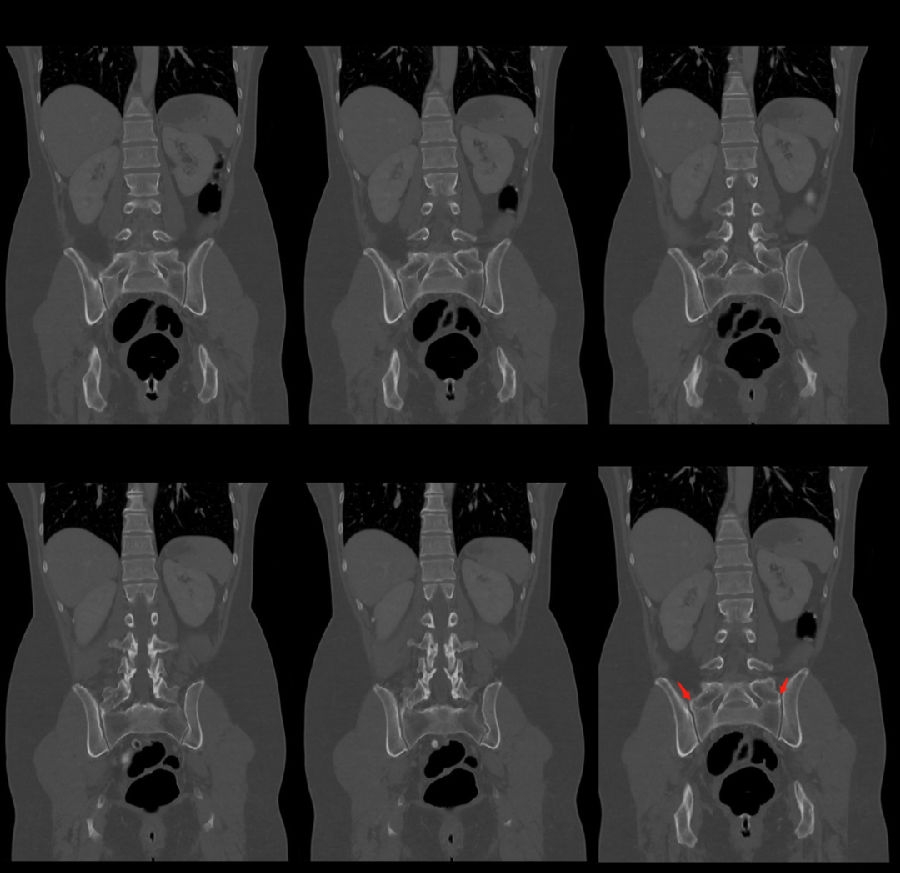

移行椎一般不引起症状,但是这种畸形可影响脊柱的稳定并逐渐产生症状,移行椎较正常椎体潜在着更多不稳。由于负重及运动不平衡,而引起腰痛。

它与腰骶部疼痛存在密切的相关性是不可忽视的,并干扰诊断与之症状相近的其它疾病,如椎间盘突出、致密性骨炎、强直性脊柱炎等等,当然这其中有些疾病可以并存,X线、CT检查在腰骶部移行椎的诊断中有重要意义,不仅能对本病做出诊断,并且有助于鉴别诊断。